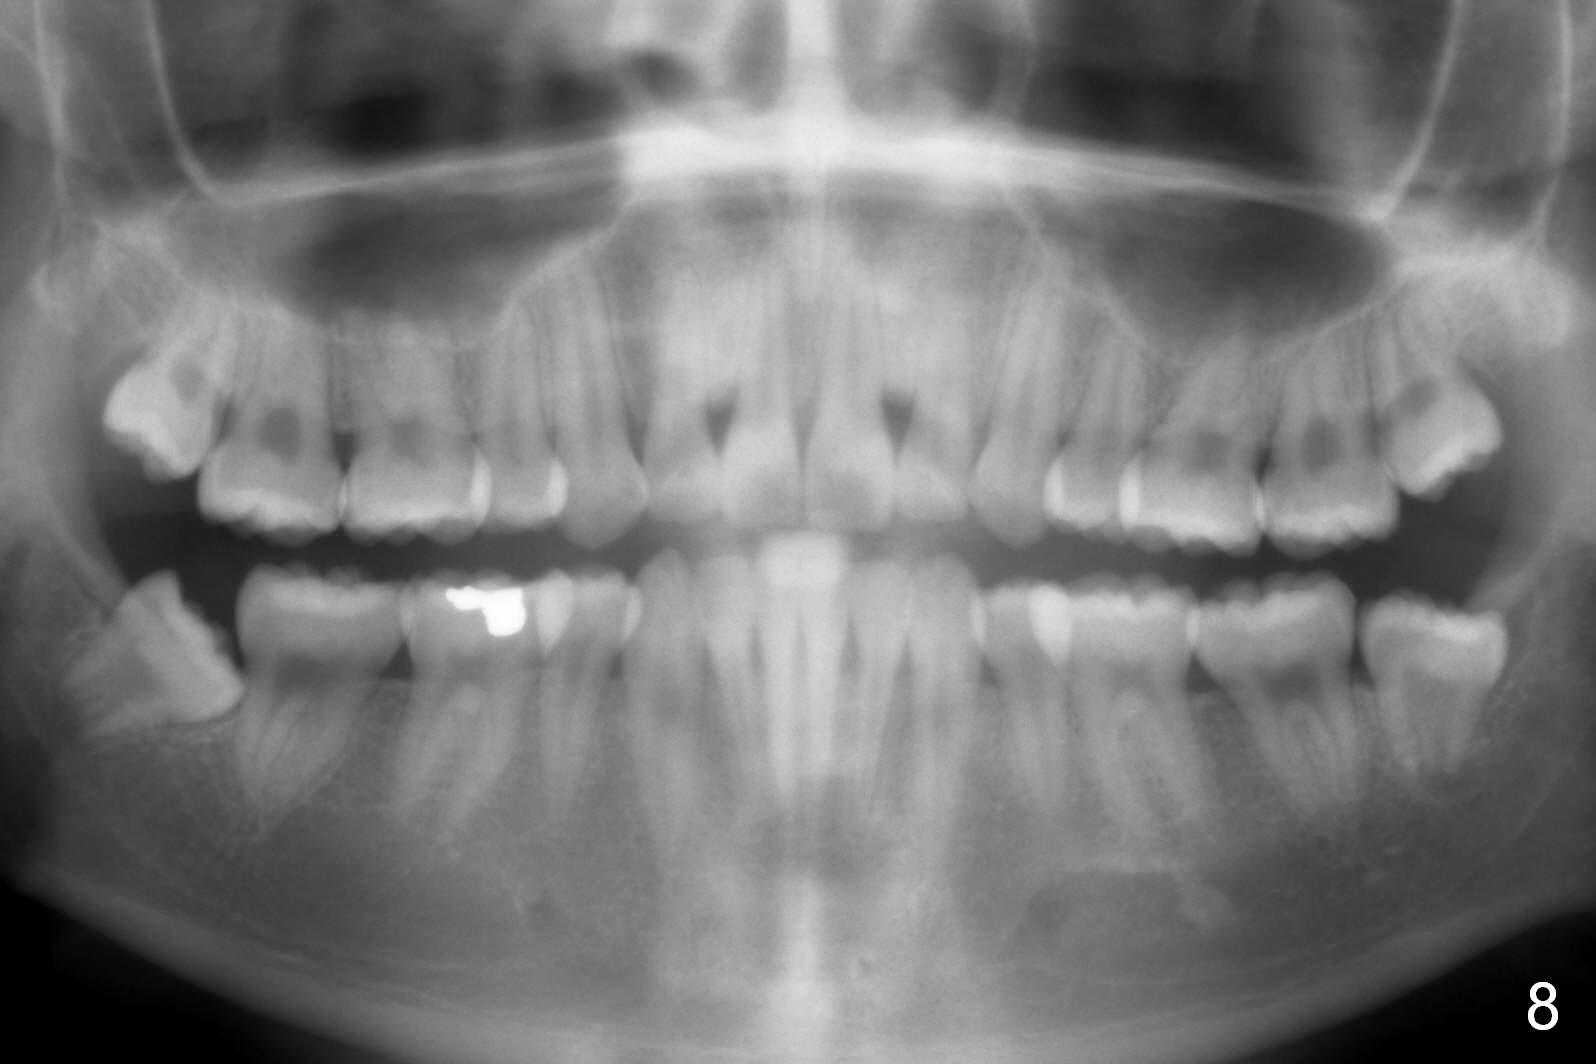

How to Take Before and After Photos for Orthodontics

First of all, before & after photos should include face, which provides evidence that after treatment (extraction) the facial profile improves.

Lighting should be double checked (Fig.1,2).